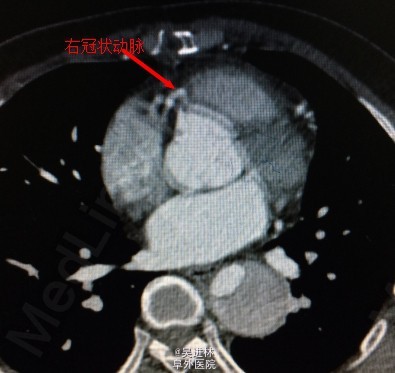

讨论:这一例病人做完手术的时候心电图显示ST段抬高,术后超声心动示左房后壁几乎无运动,于是仔细查看胸部CT,原来这个病人有三个冠状窦开口!也就是回旋支和前降支分别开口于主动脉根部,一共有3个冠状动脉开口!但是bentall手术只吻合了两个冠状窦口,造成病人心肌(左心室后壁——回旋支供血区)缺血。冠状动脉开口变异非常罕见,这真是百密必有一疏,希望大家引以为戒。二进宫时,患者右心跳动良好,左心基本无跳动,于是安置左心引流管,分流一部分血液出来,减轻左心室前负荷。